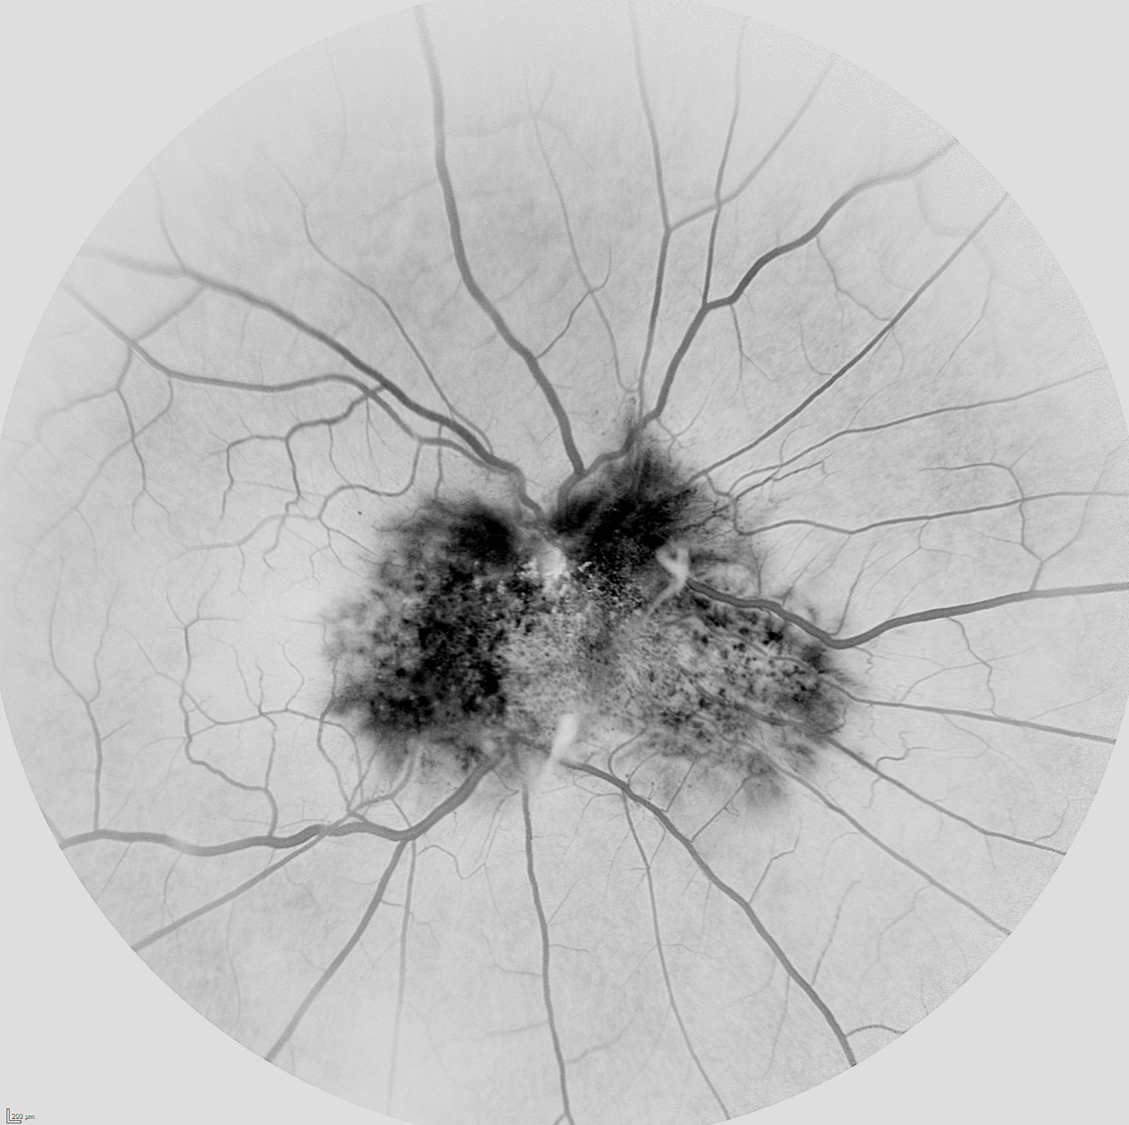

La angiografía puede ayudar bastante en el diagnóstico observándose en las fases precoces hipofluorescencia en relación al grado de hiperpigmentación del tumor, tortuosidad vascular y telangiectasias. En la fase media se observan mejor las anomalías vasculares y según avanzan los tiempos los vasos suelen fugar dando lugar a una hiperfluorescencia tardía.